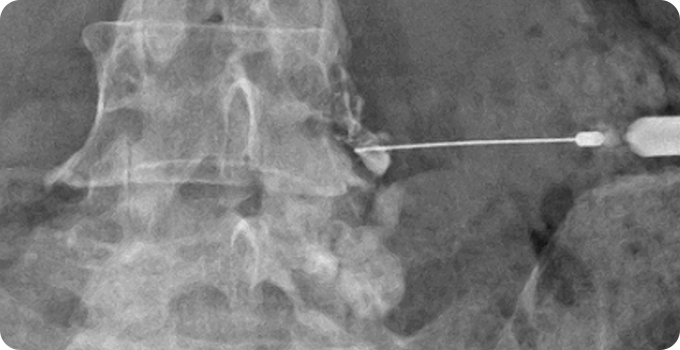

신경차단술 사진

1

신경차단술

신경에 약물을 주입해 염증과 통증을 완화하는 비수술적 치료입니다. 시술이 간단하고 비교적 안전하며, 즉각적인 통증 완화 효과를 기대할 수 있습니다. 허리디스크뿐만 아니라 척추관 협착증 등 다양한 신경통 치료에 사용됩니다. 다만, 일시적인 완화에 초점이 맞춰져 근본적인 문제 해결을 위해 추가 치료가 필요할 수 있습니다.

• 안전한

치료방법

• 즉각적인

통증 완화

• 다양한 질환

적용 가능

• 빠른

일상생활 복귀